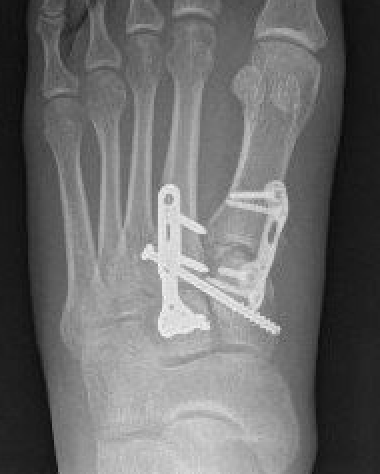

Bridge plate

Bridge plate to 1st TMT and second TMT with Lisfranc screw